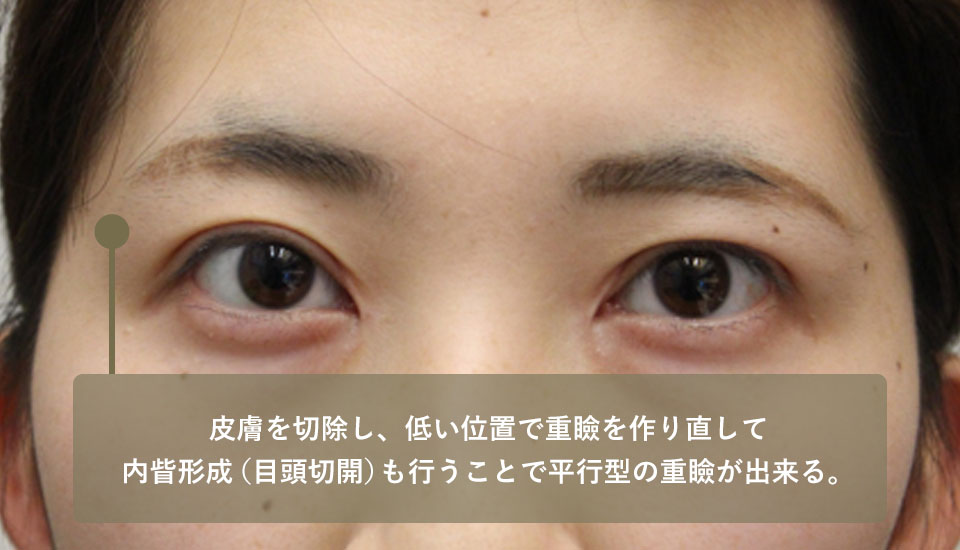

このためこの方には内眥形成術(目頭切開)と上眼瞼の皮膚切除、重瞼作成を行いました。術後、平行型の綺麗な重瞼線が出来て表情も自然になりました。

| 術前 | 二重瞼の位置が上過ぎて結局その下の皮膚がたるんでいる蒙古ひだが張っているタイプなのでここを修正しないと自然な二重瞼にならない |

|---|---|

| 術後 | 皮膚を切除し低い位置で重瞼を作り直し、内眥形成(目頭切開)も行うことで平行型の重瞼が出来た |

| 術前 | 二重瞼が高すぎるのでそれより下の皮膚が余っている蒙古ひだがあるので、目の大きさが縦横1:1になって不自然 |

|---|---|

| 術後 | 内眥形成と重瞼の作り直しをしたところ、目の大きさの比は縦横1:2くらいの自然な大きさになった |